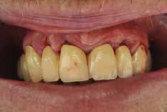

OXYSAFE® – Innovative Technologie auf Aktivsauerstoffbasis zur Behandlung von Parodontalerkrankungen

Patientensituation nach erfolgter Therapie mittels Metronidazol, CHX Chips, aPDT und anderen Maßnahmen nach dem 3. Recall

Applikation des OXYSAFE Gels in situ Patientensituation 3 Wochen nach Beginn der Sauerstofftherapie mittels OXYSAFE

OXYSAFE® Professional Gel und Liquid

Zur nachhaltigen Unterstützung in der Behandlung von Parodontitis und Periimplantitis

• Gel und Mundspülung mit aktiver Sauerstofftechnologie

• Schnelle Reduktion der Taschentiefe

• Taschendesinfektion und beschleunigte Wundheilung

• Einfache und präzise Applikation

Fallbericht

Ein 55-jähriger Patient kommt zur ersten Untersuchung in die Klinik der Abteilung für Parodon tologie des Klinischen Krankenhauses Zagreb. Er ist Raucher und hat keine systemischen Erkran kungen. Die Begutachtung des Orthopantomogramms und klinische Untersuchung weisen auf eine Parodontitis hin.

VorherNachher

Beispielhaft nun die Anwendug von OXYSAFE am Frontzahn

11. Die Sondierungstiefe beträgt sowohl mesial als auch distal 7 mm an Zahn 11 und es liegt eine Blutung vor. Es liegt ein vertikaler Knochenverlust vor.

Reinigen der Zahnfleischtasche Erste direkte Applikation des Gels in die Zahnfleischtasche Fortsetzung der Behandlung durch den Patienten zuhause 3 täglich 10 ml Zweite Applikation des Gels in die Zahnfleischtasche und dort belassen >> Keine Antibiotika >> Kein CHX >> Über 20 Jahre klinische Erfahrung ca. 2,74 € pro Zahnfleischtasche Aktion Jetzt gratis testen!*